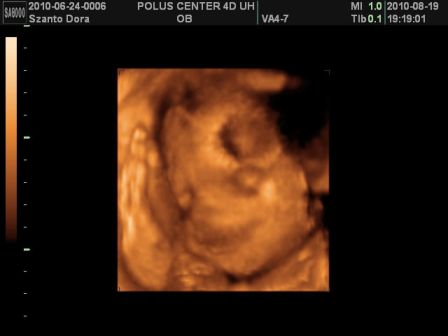

Basszus! Hívtam a kórházat, kiderült a dokim szabin, csak jövő héten szerdán lesz, de menjek be mindenképpen az ügyeleteshez! Na, anyuval felkerekedtünk és irány a kórház. Először csináltak egy uh-t! Dani épp fent volt és akkorákat rúgdalt, h patogott a nőci kezében a vizsgáló kütyü!

Megint nagyobbra mérték egy héttel, szóval továbbra is tartjuk a november elejét, mint születés. És farfekvéses a drágám egyelőre...

Viszont, most már 1360g volt a súlya az 1 héttel ezelőtti 1160g-hoz képest!